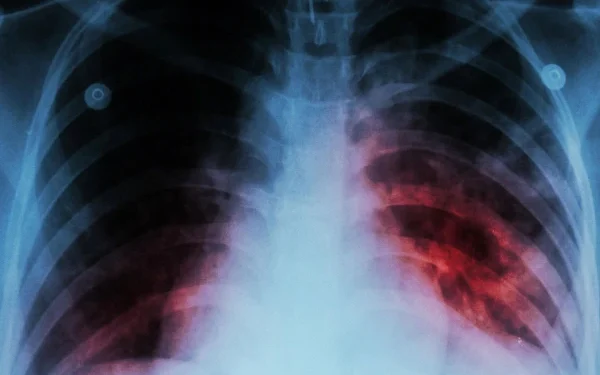

According to the World Health Organization, more than 8 million people were diagnosed with TB last year. This is the highest number recorded since the institution started records.

According to the latest report, about 12 lakh 50 people died of TB last year. While TB is likely to become the world’s deadliest pandemic again. This number of deaths is almost double the number of people who will die from HIV in 2023.

The World Health Organization said that the region of Southeast Asia, Africa and the Western Pacific is affected more by the cause of TB. India, Indonesia, China, Philippines and Pakistan account for more than half of the total cases worldwide.